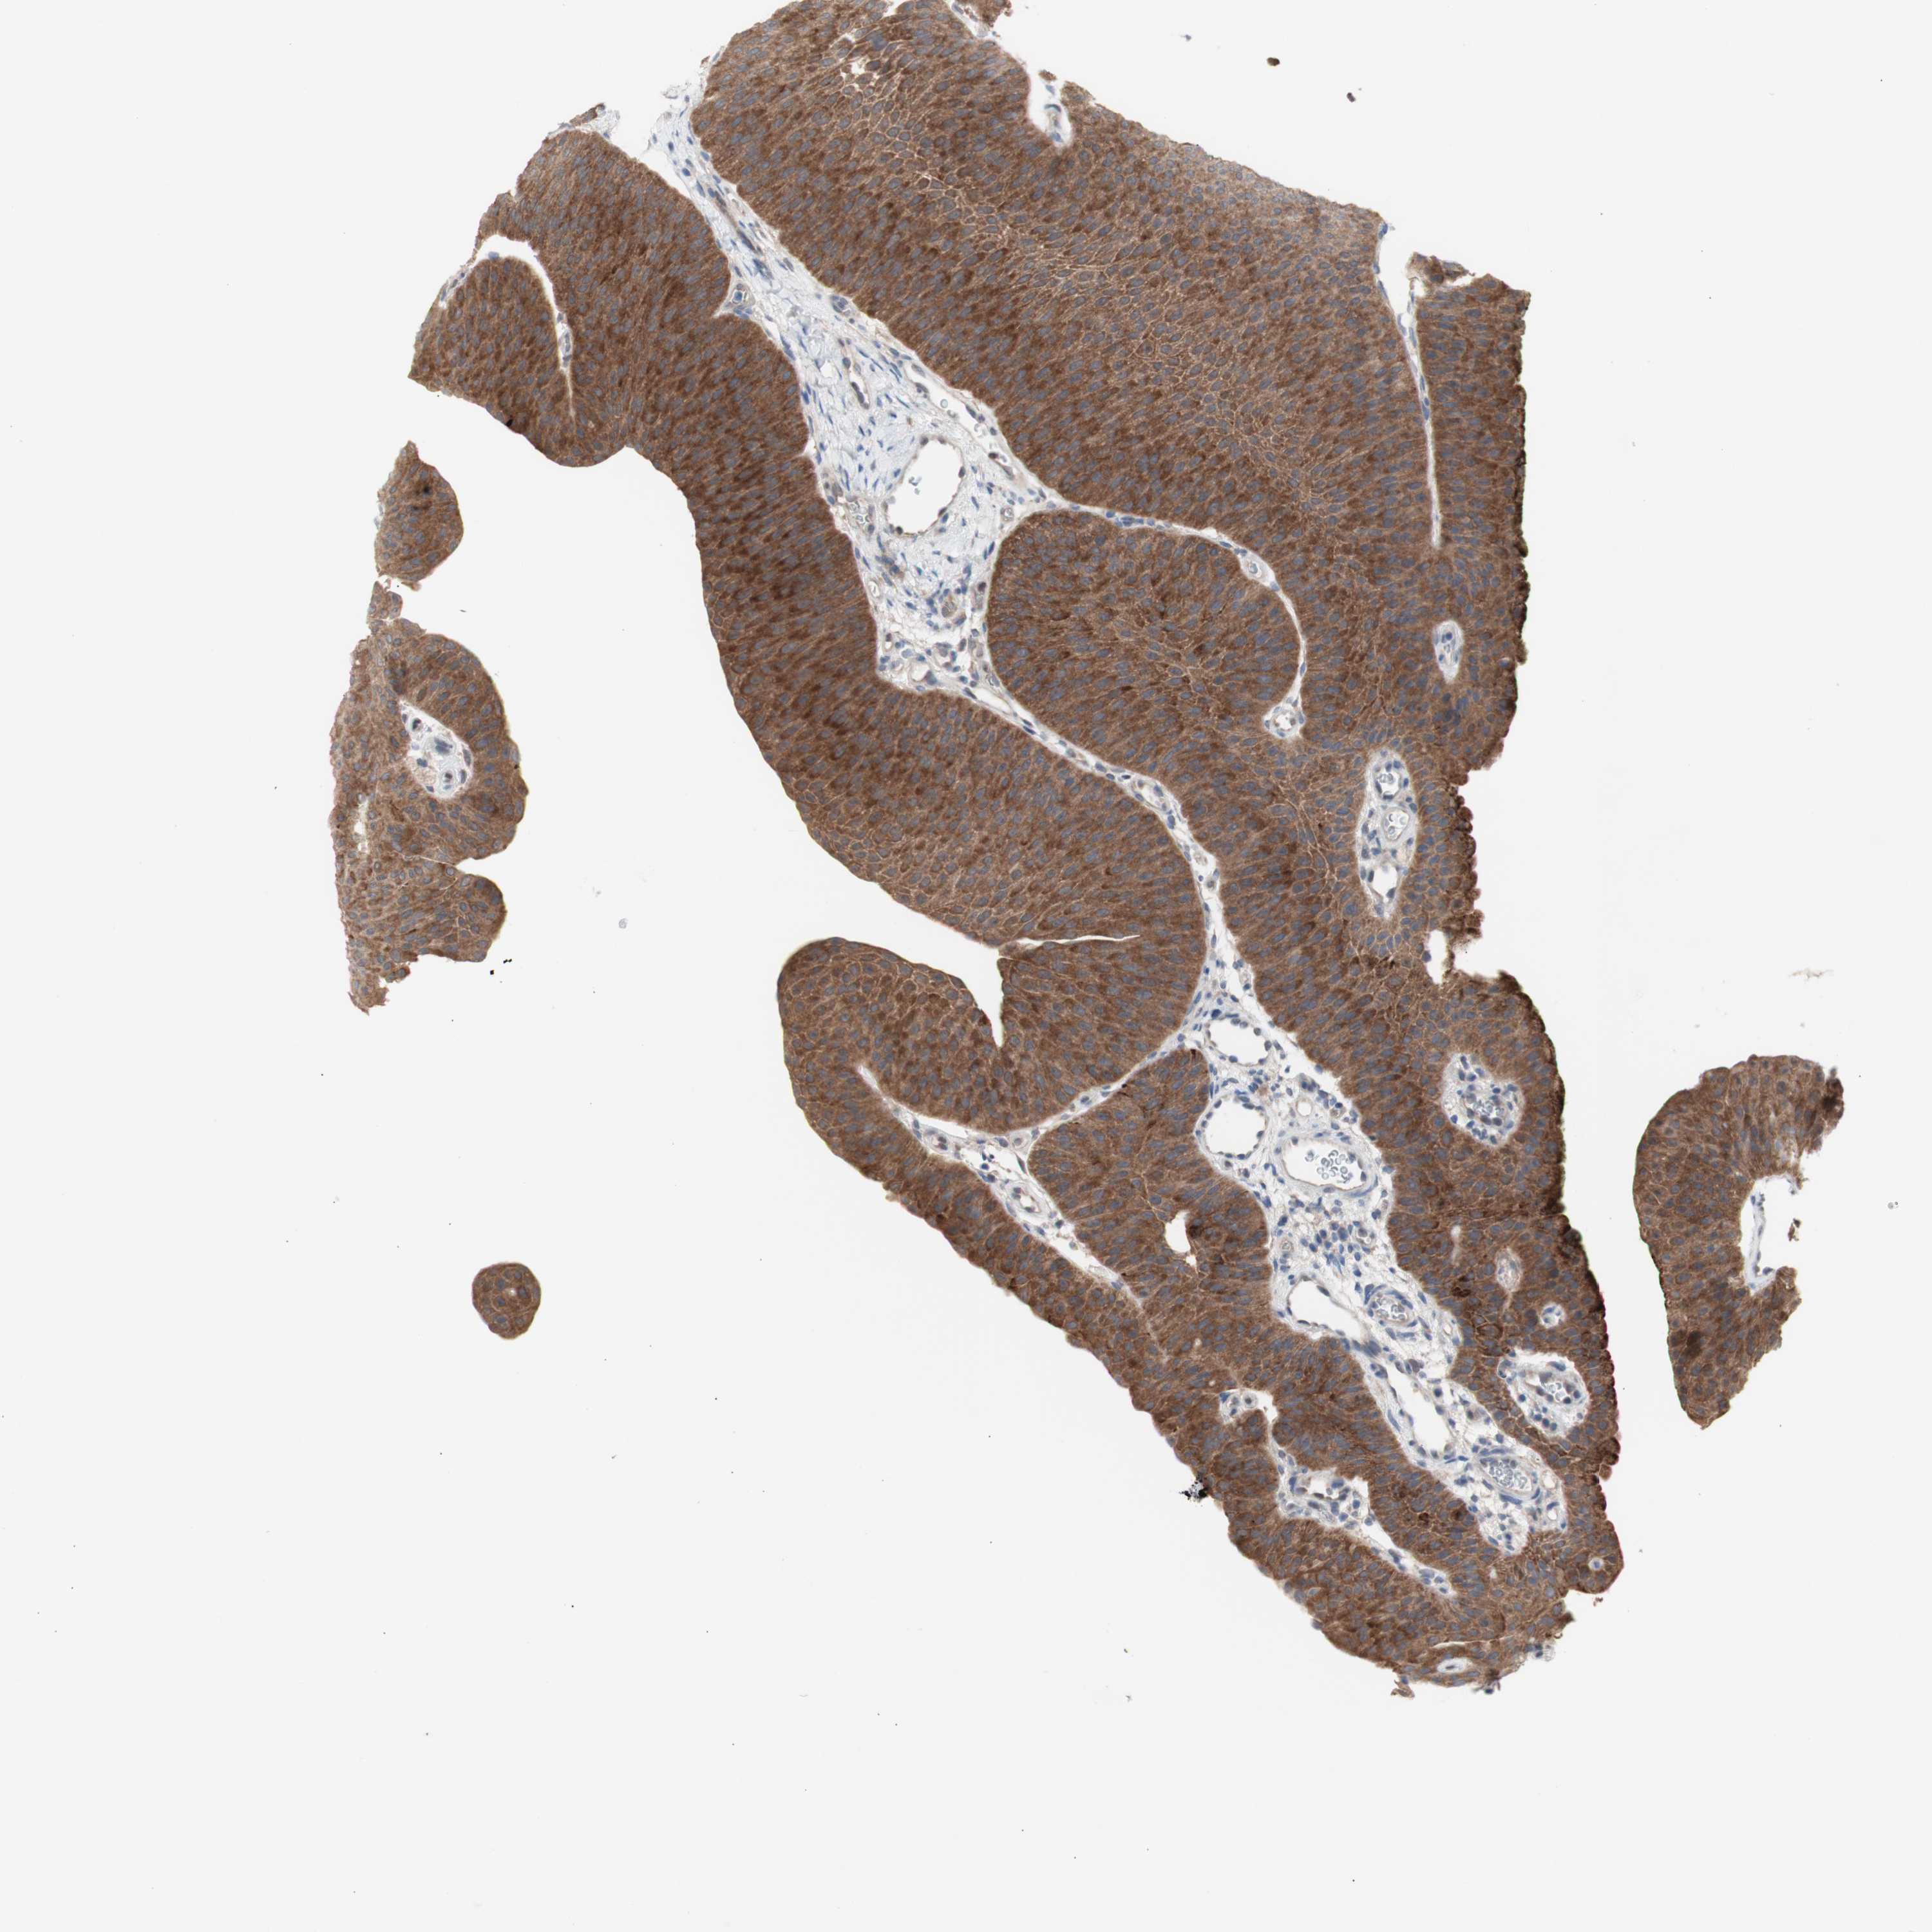

UROTHELIAL CANCER - Protein expressioni

A mouse-over function shows sample information and annotation data. Click on an image to view it in a full screen mode. Samples can be filtered based on level of antibody staining by selecting one or several of the following categories: high, medium, low and not detected. The assay and annotation is described here.

Note that samples used for immunohistochemistry by the Human Protein Atlas do not correspond to samples in the TCGA dataset.

Antibody stainingi

Antibody staining in the annotated cell types in the current human tissue is reported as not detected, low, medium, or high, based on conventional immunohistochemistry profiling in selected tissues. This score is based on the combination of the staining intensity and fraction of stained cells.

Each image is clickable and will lead to virtual microscopy that enables deeper exploration of all samples and also displays staining intensity scores, fraction scores and subcellular localization as well as patient and tissue information for each sample.

Antibody HPA005525

Antibody HPA064708

Antibody CAB012459

Staining

High

Medium

Low

Not detected

Intensity

Strong

Moderate

Weak

Negative

Quantity

>75%

75%-25%

<25%

None

Location

Nuclear

Cytoplasmic/membranous

Cytoplasmic/membranous,nuclear

Urothelial carcinoma, High grade

Urothelial carcinoma, Low grade

Urothelial carcinoma, NOS